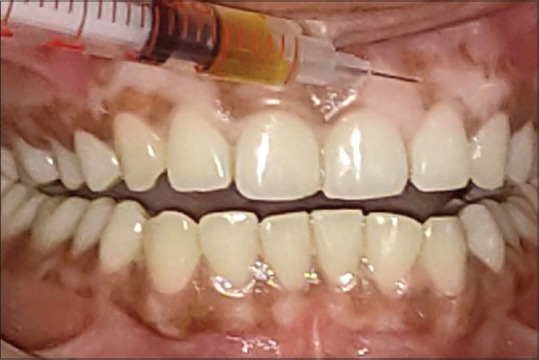

Materials and methods: Individuals with complaint of black gums were included. Informed consent was obtained. Initial treatment of scaling and root planing was conducted and they were recalled after 2 weeks. The gingival depigmentation was performed by scalpel technique. The excised layer of epithelial tissue was sent to the laboratory to assess the Tyr and TRP-1 levels. Subsequently, Vitamin C was administered at monthly interval for 6 months. Tyr and TRP-1 levels were assessed at the end of 1 year follow-up.